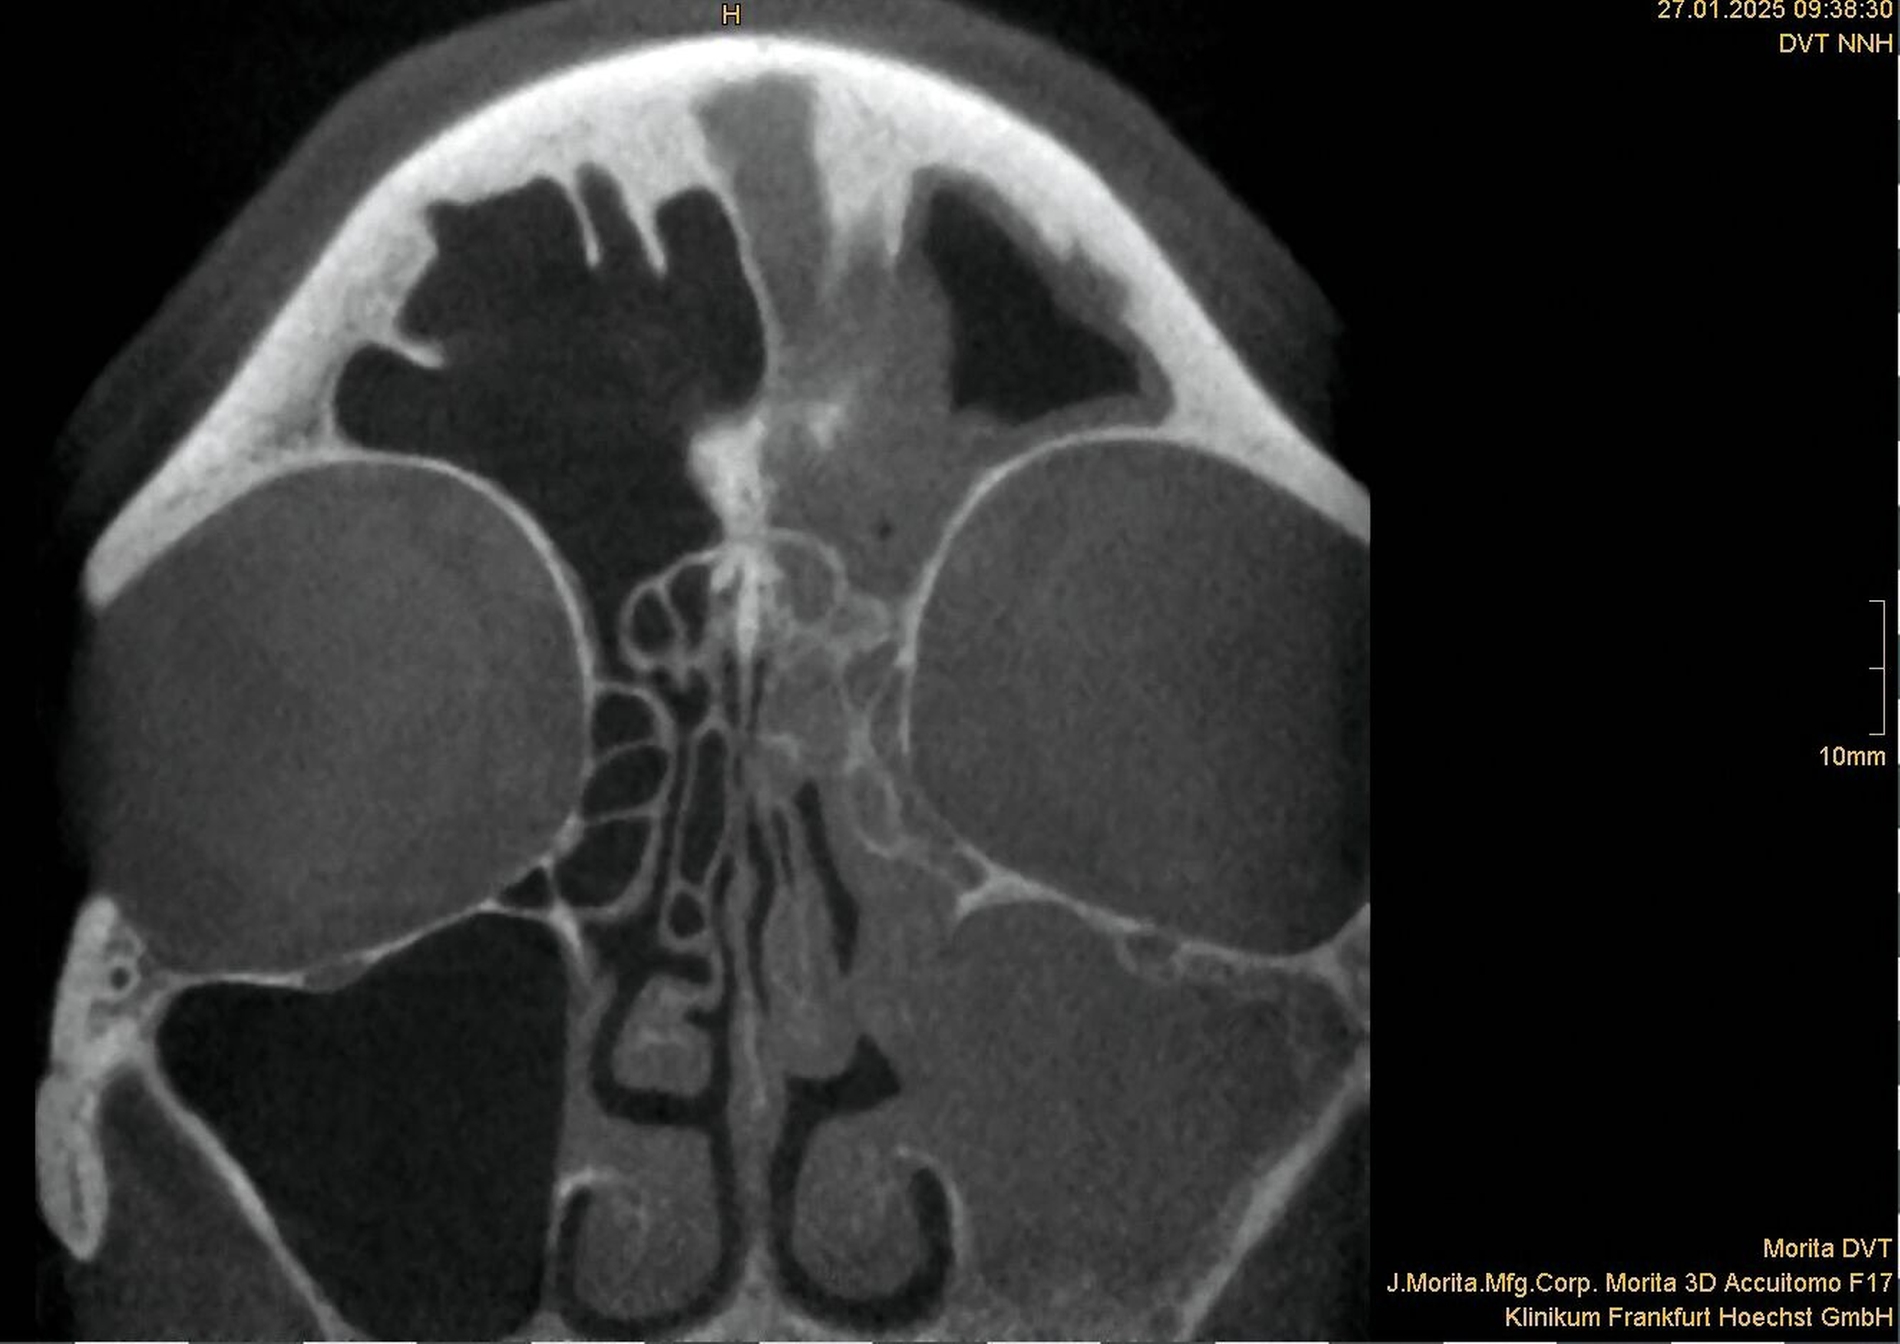

Zwischen März und Oktober 2022 erfolgten dort eine Wurzelkanalbehandlung und später eine Revision an Zahn 26 sowie eine Trepanation von Zahn 27 mit Abfluss von putridem Sekret. Trotz dieser Maßnahmen blieben die Beschwerden bestehen. Ein DVT im Mai 2023 zeigte eine zystische Läsion in regio 27 mit Verdacht auf Kieferhöhlenperforation und bereits vollständiger Verschattung der linken Kieferhöhle (Abbildung 2). Zahn 27 wurde daraufhin extrahiert.